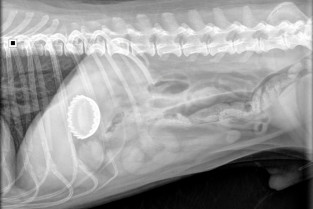

Nos deux intervenantes diplômées ECVID, Laure GATEL et Anaïs COMBES vont une nouvelle fois vous entraîner de façon dynamique et pédagogigue dans des cas cliniques qui exerceront votre œil et vous apporteront des arguments solides afin de savoir différencier une occlusion d'une subocclusion, diagnostiquer sans hésiter une torsion d'estomac, de mésentère ou de côlon et reconnaître de façon assurée les lésions bénignes et malignes fréquentes du tube digestif.

- différencier iléus paralytique et mécanique, et diagnostiquer un corps étranger digestif ;